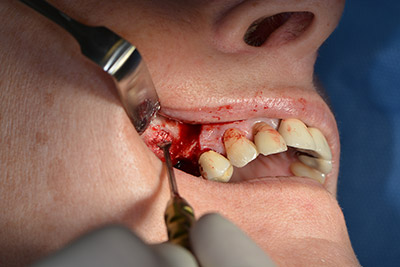

Класическият разрез (крестално, букално освобождаване) и подготовката на мукопериостално ламбо осигуряват добра видимост.

Импланти Sky (Bredent) са използвани в този случай. Хирургичният протокол за тях изисква пилотно пробиване с дрил при 1200 rpm (Фиг. 9).